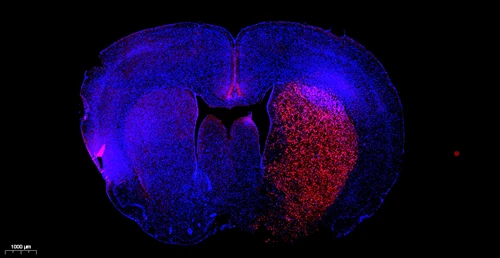

The breakage of chromosomal DNA in apoptosis is a gradual process. Chromosomal DNA is first degraded into large fragments of 50-300 kb under the action of endogenous nucleases, and then about 30% of chromosomal DNA is under the action of Ca2+ and Mg2+-dependent endonucleases. They are randomly cut to form 180-200 bp nucleosomal DNA polymer. Therefore, in the late stage of apoptosis, DNA will be degraded into 180-200 bp fragments, and a large number of 3'-OH ends will be exposed on the broken genomic DNA. Terminal Deoxynucleotidyl Transferase (TdT) is a template-independent DNA polymerase that can catalyze the binding of deoxynucleotides to the 3'-OH ends of broken DNA molecules. Therefore, TUNEL (TdT mediated dUTP Nick End Labeling) cell apoptosis detection kit can be used to detect the nuclear DNA breakage of tissue cells in the late stage of apoptosis. The principle is that under the action of TdT enzyme, tetramethyl-Rhodamine-dUTP (Tetramethyl-Rhodamine-5-dUTP, TMR-5-dUTP) is incorporated into the 3´-OH end exposed when genomic DNA is broken, so that it can be Detect with a fluorescence microscope or flow cytometer (TMR excitation 520-560 nm, emission 570-620 nm). This kit has a wide range of applications and is suitable for the detection of cell apoptosis in paraffin tissue sections, frozen tissue sections, cell slides, cell smears, etc.